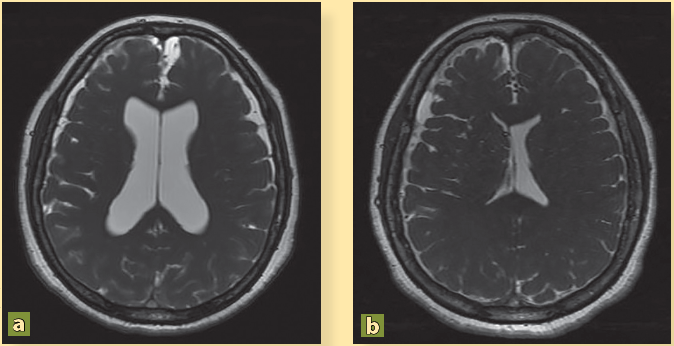

La paciente presenta mejoría clínica y es egresada por remisión de la cefalea y de las crisis convulsivas tras 16 días de estancia hospitalaria con indicaciones de continuar con esteroides vía oral y fármacos anticomiciales. Por iniciativa propia, la paciente no acudió a sus citas de seguimiento durante 4 años. Después, y debido a que ha presentado cefalea con intensidad 10/10, náusea y vómito constantes, desorientación y alteraciones del lenguaje, y varios episodios convulsivos, es traída por sus familiares al servicio de urgencias. Los familiares informaron que el tratamiento médico fue abandonado y optaron por una terapia de medicina naturista. Se ingresó la paciente y la nueva RM mostró persistencia de los cisticercos (figuras 2A, 2C, 3A, 4A) así como dilatación de los ventrículos (figura 5A). Se colocó una derivación ventrículo peritoneal (DVP) (figura 5B) y se inició nuevo tratamiento con albendazol (15 mg/kg), praziquantel (50 mg/kg) por 10 días, y dexametasona (8 mg/8h). Tras 40 días de estancia hospitalaria, se decidió su egreso con cita en la consulta externa.

Dilatación de los ventrículos laterales en un caso de NCC (a) y la normalización del tamaño ventricular después de la colocación de una válvula de derivación ventrículo-peritoneal (b).

Figura 5 Resonancia magnética secuencia FIESTA

El resultado del tratamiento fue parcial y la paciente requirió de 8 ciclos de albendazol para poder inactivar la NCC. En la RM de 2019 se mostró la remisión total de los parásitos y la ausencia de hidrocefalia (figuras 2B, 2D, 3B, 4B). Actualmente la paciente se mantiene estable, sin cefaleas, ni eventos convulsivos y con un buen funcionamiento de la DVP.